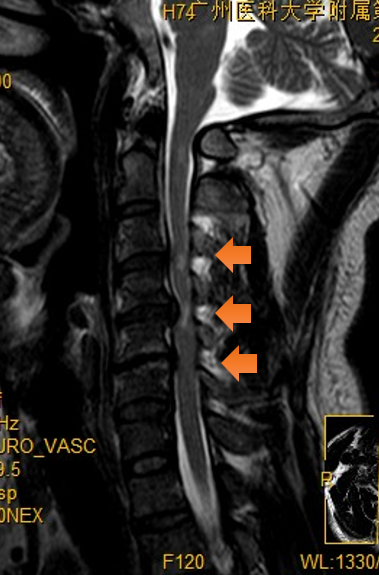

近日,他前往广州医科大学附属第三医院就诊,医生为他详细做了体格检查和影像学检查,发现他的问题竟出在颈椎上,属于脊髓型颈椎病,如果不尽早干预,任其发展下去,严重时甚至可致瘫痪。

陈伯被确诊为脊髓型颈椎病(橙色箭头是颈椎管狭窄处)。